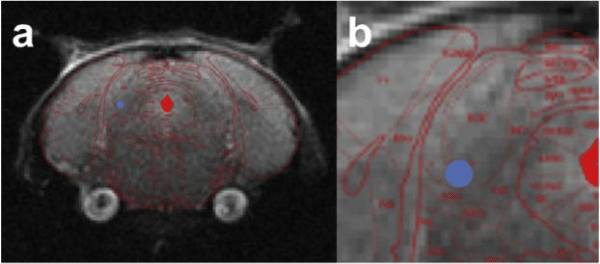

Figure 3:

Insertion location of electrode in right hemipshere. a) Whole brain coverage of location for probe insertion. b)Simulated probe location (AP = -4.70 mm Bregma, ML = 1.50 mm and DV = -2.50 mm Bregma).